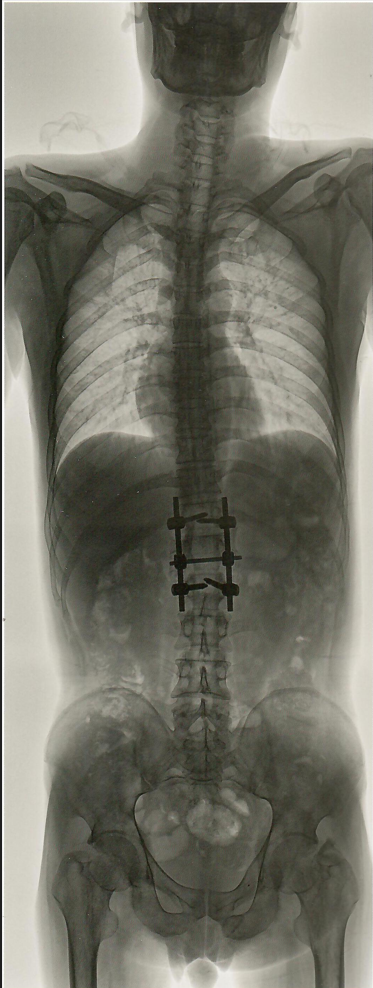

新东方摄影X射线机,开启DR“百微世界”,大尺寸平板精准成像,展现超越肉眼的丰富细节,3秒成像,超高清晰度和非凡的图像细节,十轴联动,六向跟踪,智导操控,本机具有国内最先进的智能一键自动拼接,管球无位移,消除运动误差,提高拼接成功率,重叠区域面积小,减少曝光次数,减少辐射剂量,采用AEC自动曝光和影像均衡算法,保证图像统一亮度和对比度。

脊柱侧弯和下肢负重骨骼畸形,矫正术前术后的全景摄影能直观的反映病变的程度和部位,为临床提供可靠诊断依据。